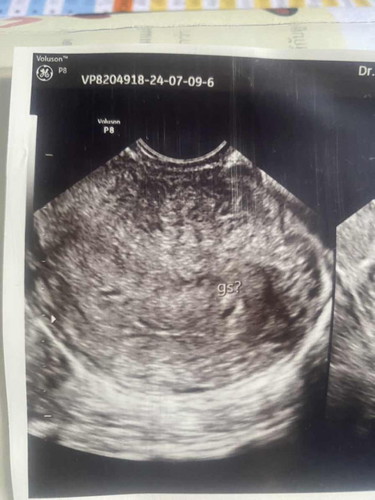

ขออนุญาติสอบถามค่ะ ตั้งครรภ์ได้5วิคยังไม่เจอถุงไข่แดงค่ะ อัลตร้าซาวผ่านช่องคลอดเจอถุงตั้งครรภ์เล็กๆ มีแม่ๆคนไหนเป็นแบบนี้มั้ยคะ ท้องที่2ค่ะ ท้องแรกท้องลม ใจคอไม่ดีเลยค่ะ หมอทางคลินิกบอกว่าท้องในมดลูกจริง อีก2อาทิตย์นัดซาวอีกทีว่าจะโตไหม#ขอบคุณสำหรับคำคอมเม้นล่วงหน้าค่ะ